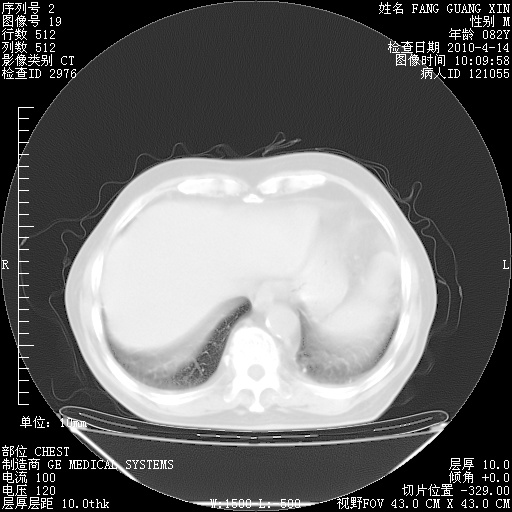

4月14日肺部CT